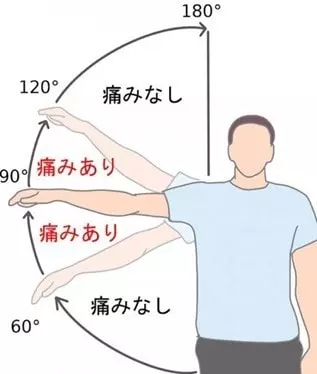

肩を動かす際、特に横に60度から120度の間で痛みを感じることがあり、これを「有痛弧徴候(ペインフルアーク)」と呼びます。